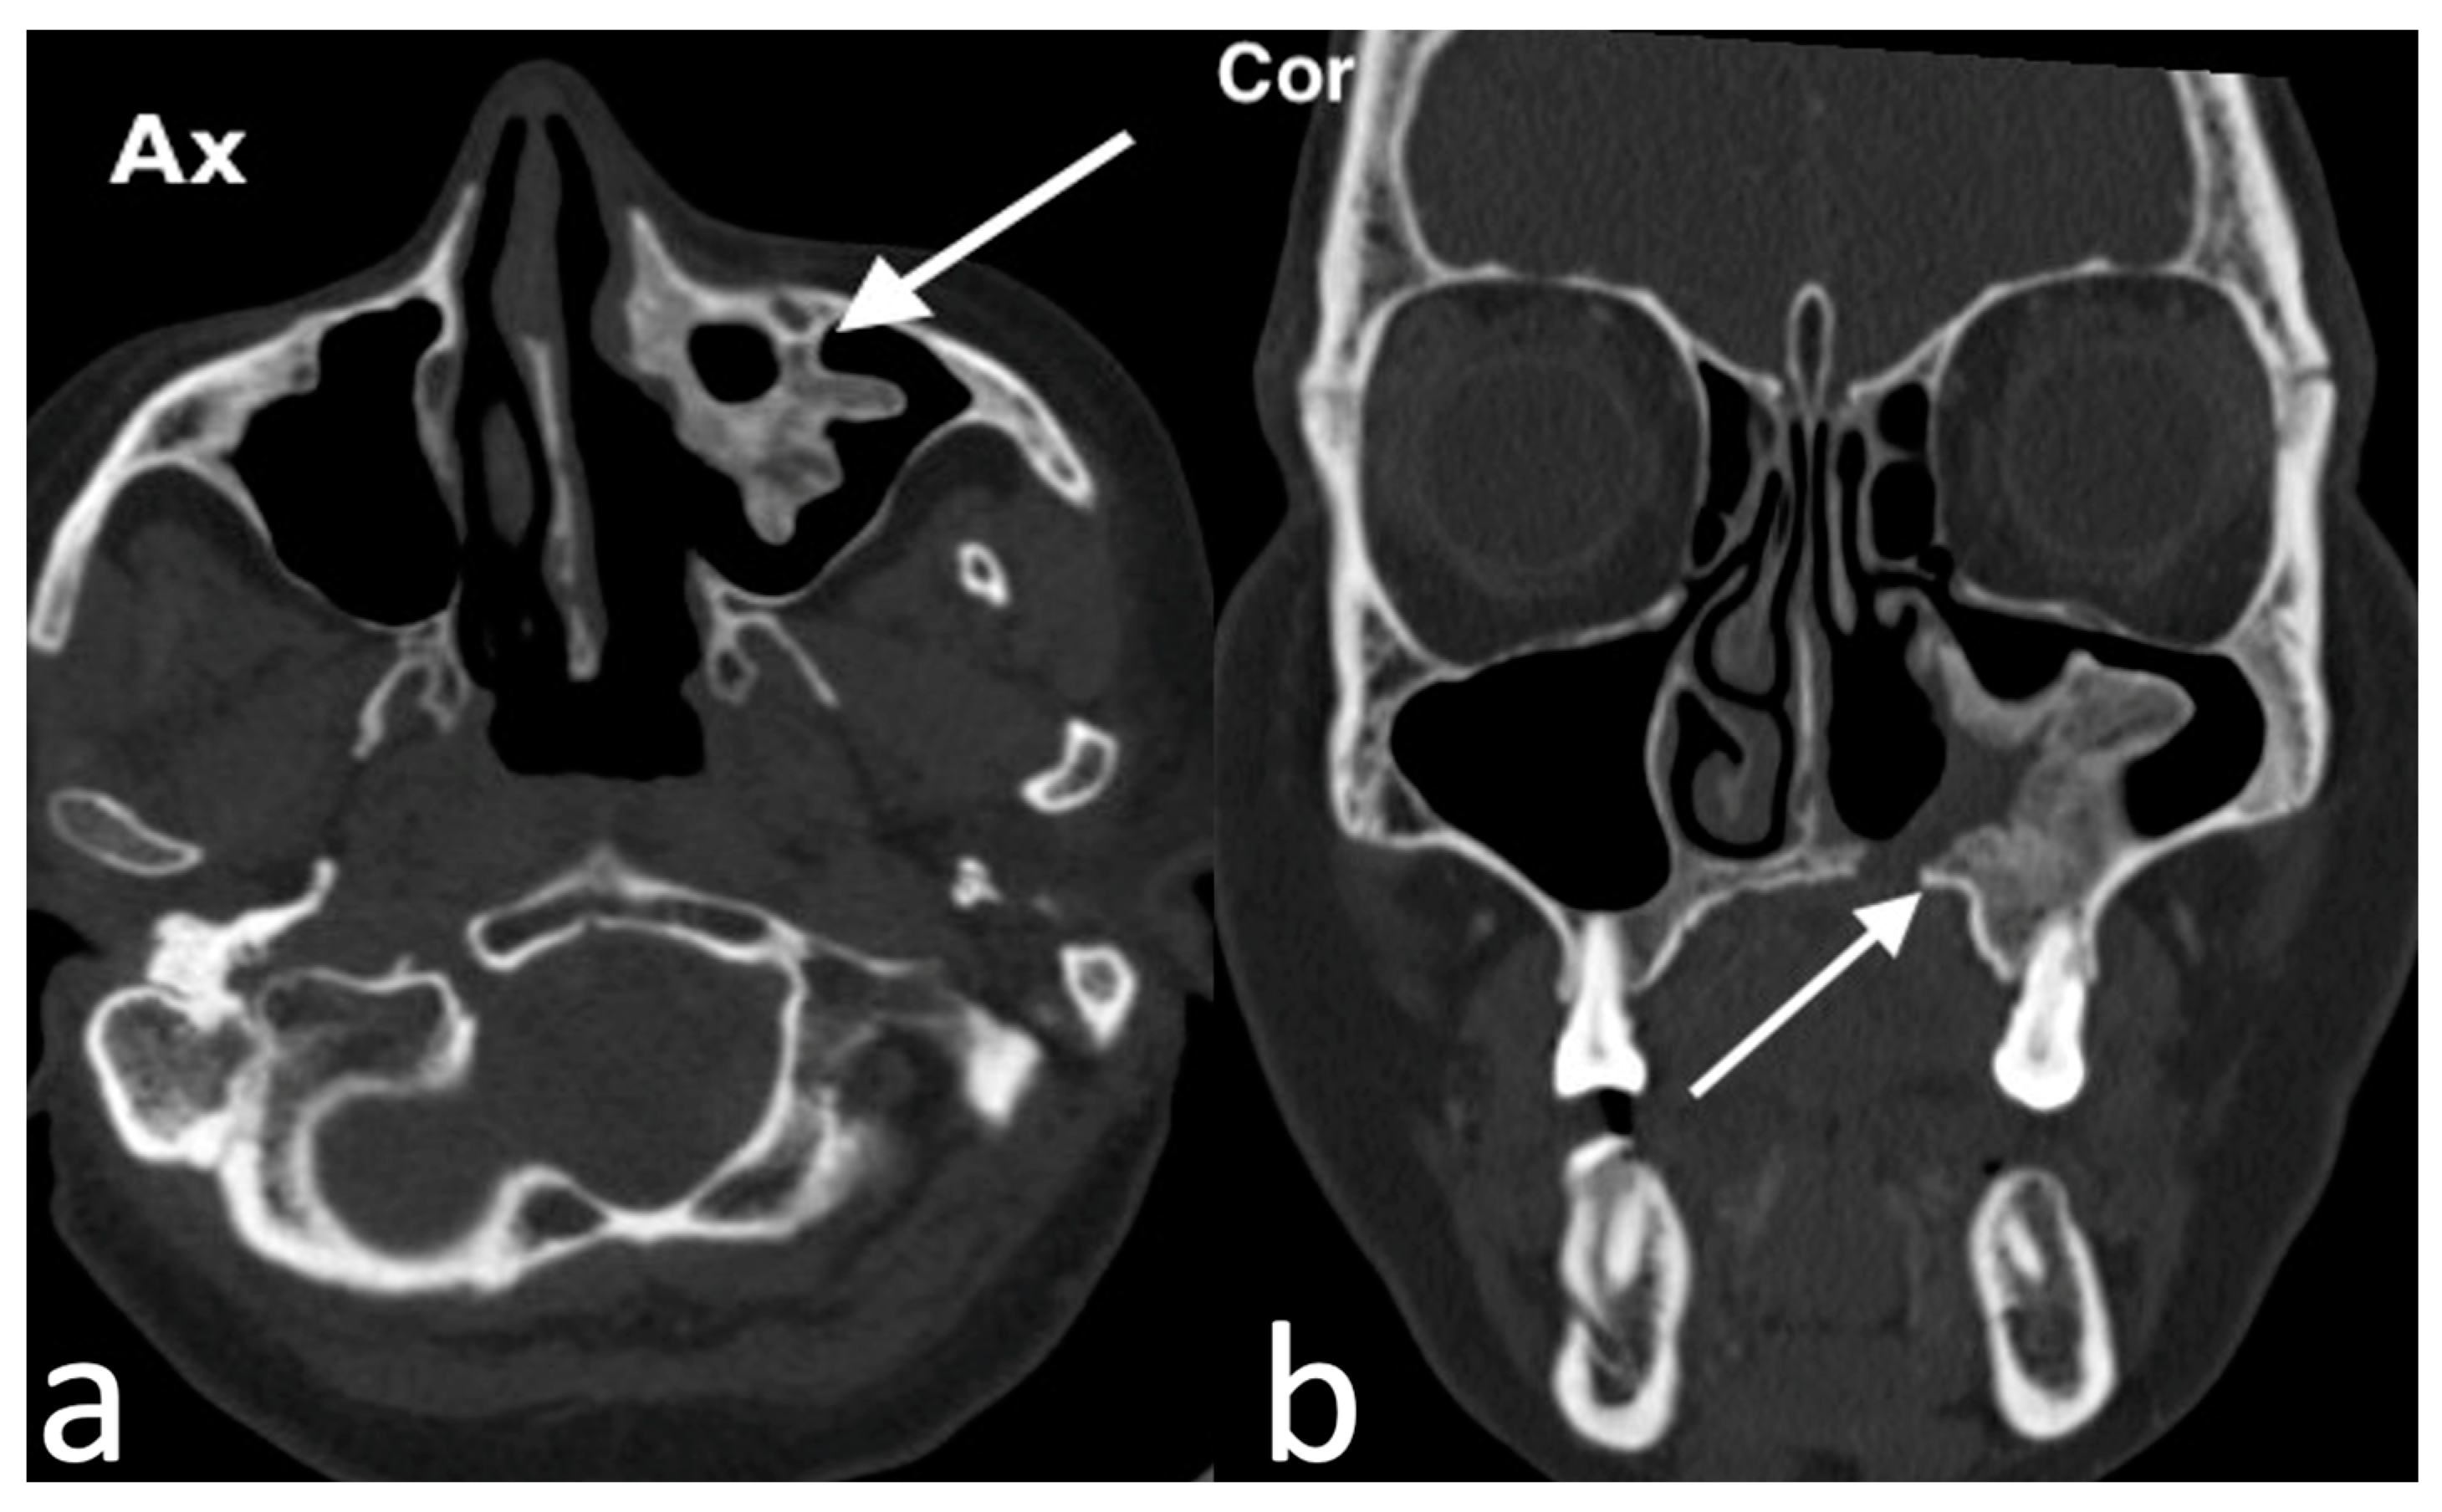

3.1.2. Rinolith